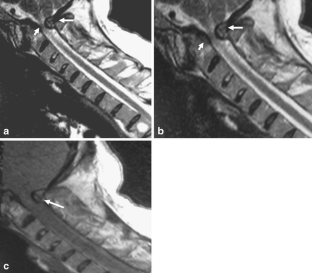

Fig. 1